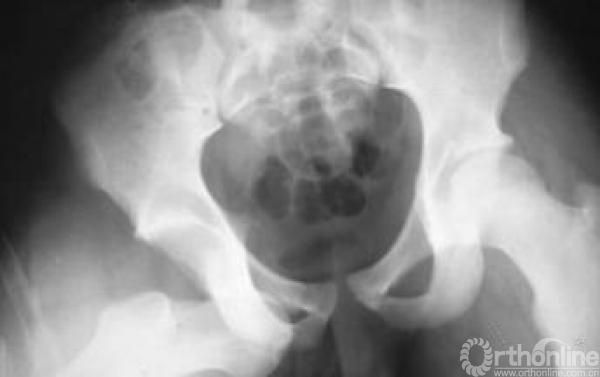

髋关节脱位主要分为后脱位和前脱位,80%都为后脱位。

最常见的仪表盘类损伤常伴随后脱位,需要行X线进行脱位的确诊。

后脱位有的是由旋转暴力,有的是由垂直暴力所引起。